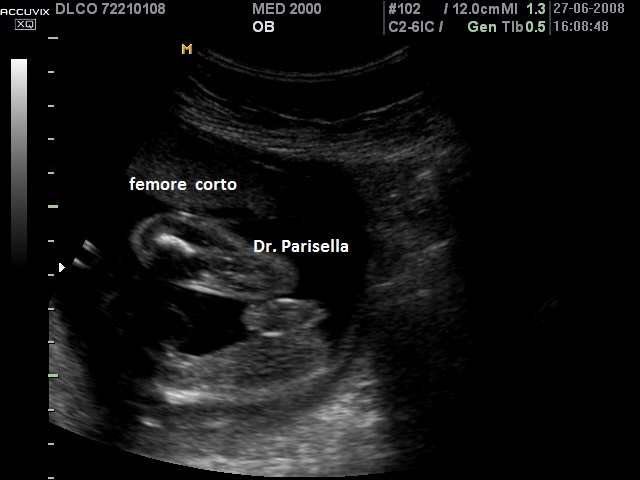

Sindrome o Complesso Femore-Fibula-Ulna OMIM 228200

E' una rara sindrome malformativa caratterizzata da difetti, ipoplasia o aplasia, di femore, fibula e ulna ai quali possono associarsi difetti delle dita.  I difetti delle dita, se presenti, interessano il lato ulnare e/o quello fibulare. Viene classificata in quattro gruppi in base all'interessamento di uno, due, tre o quattro arti.

L'interessamento di femore, fibula ed ulna è caratteristico ma possono essere interessate anche le altre ossa lunghe: la mano (aplasia), la tibia (ipoplasia) e l'omero (ipoplasia).

La coesistenza dell'interessamento di questi tre segmenti ossei da soli è sufficiente a porre la diagnosi di Sindrome o Complesso Femore-Fibula-Ulna, indipendentemente dall'interessamento o meno di altri segmenti ossei. La triade femore-fibula-ulna è patognomonica della patologia.